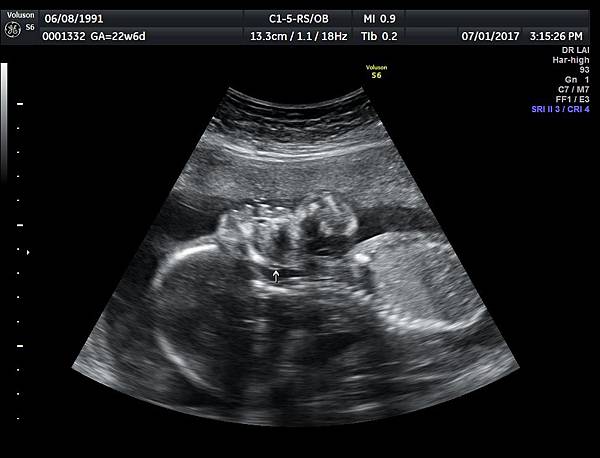

• 孕兒診所備忘錄 261 2017 07 palate , uvula and lip images

2017 07 palate , uvula and lip images

uvula of soft palate